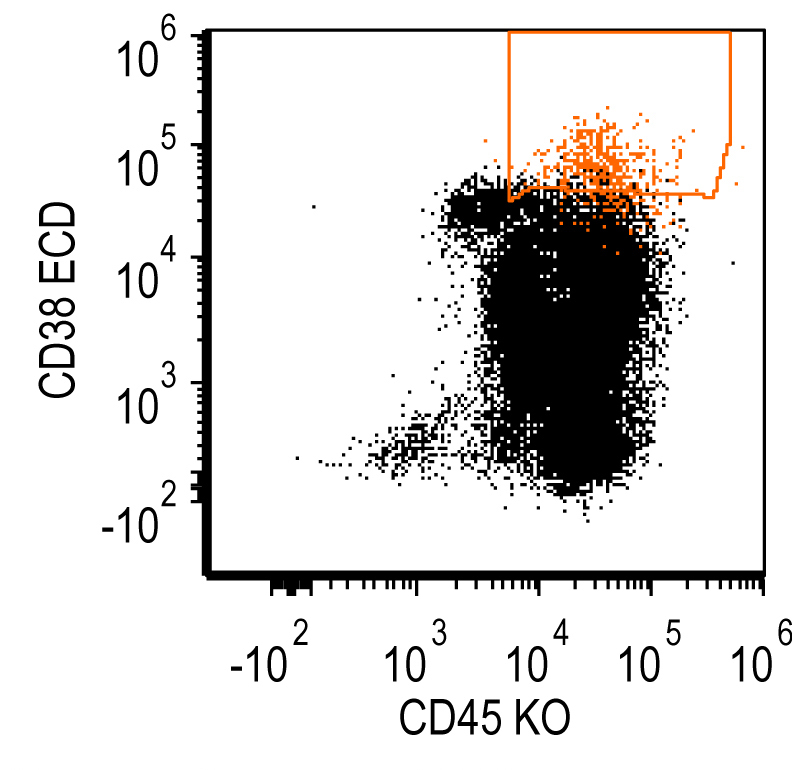

- Flow cytometry: monoclonal B cells with typical immunophenotype and monoclonal plasma cells

- Immunophenotype of LPL cells: IgM+, CD19+, CD20+, CD22+, CD25+, CD10-, CD23-, CD103-, variable CD138

- Immunophenotype

- Positive: IgM, CD19, CD20, CD22, CD79a, CD25 and CD38 frequent expression

- Negative: CD5, CD10, CD103, CD23; however, CD23 expression is not uncommon in some cases

- Plasma cells in lymphoplasmacytic lymphoma

- Positive: CD138, CD19, CD45 and sometimes MUM1 but can be negative

Flow cytometry description

Flow cytometry images

Contributed by Ling Zhang, M.D. and Caroline An, M.D.